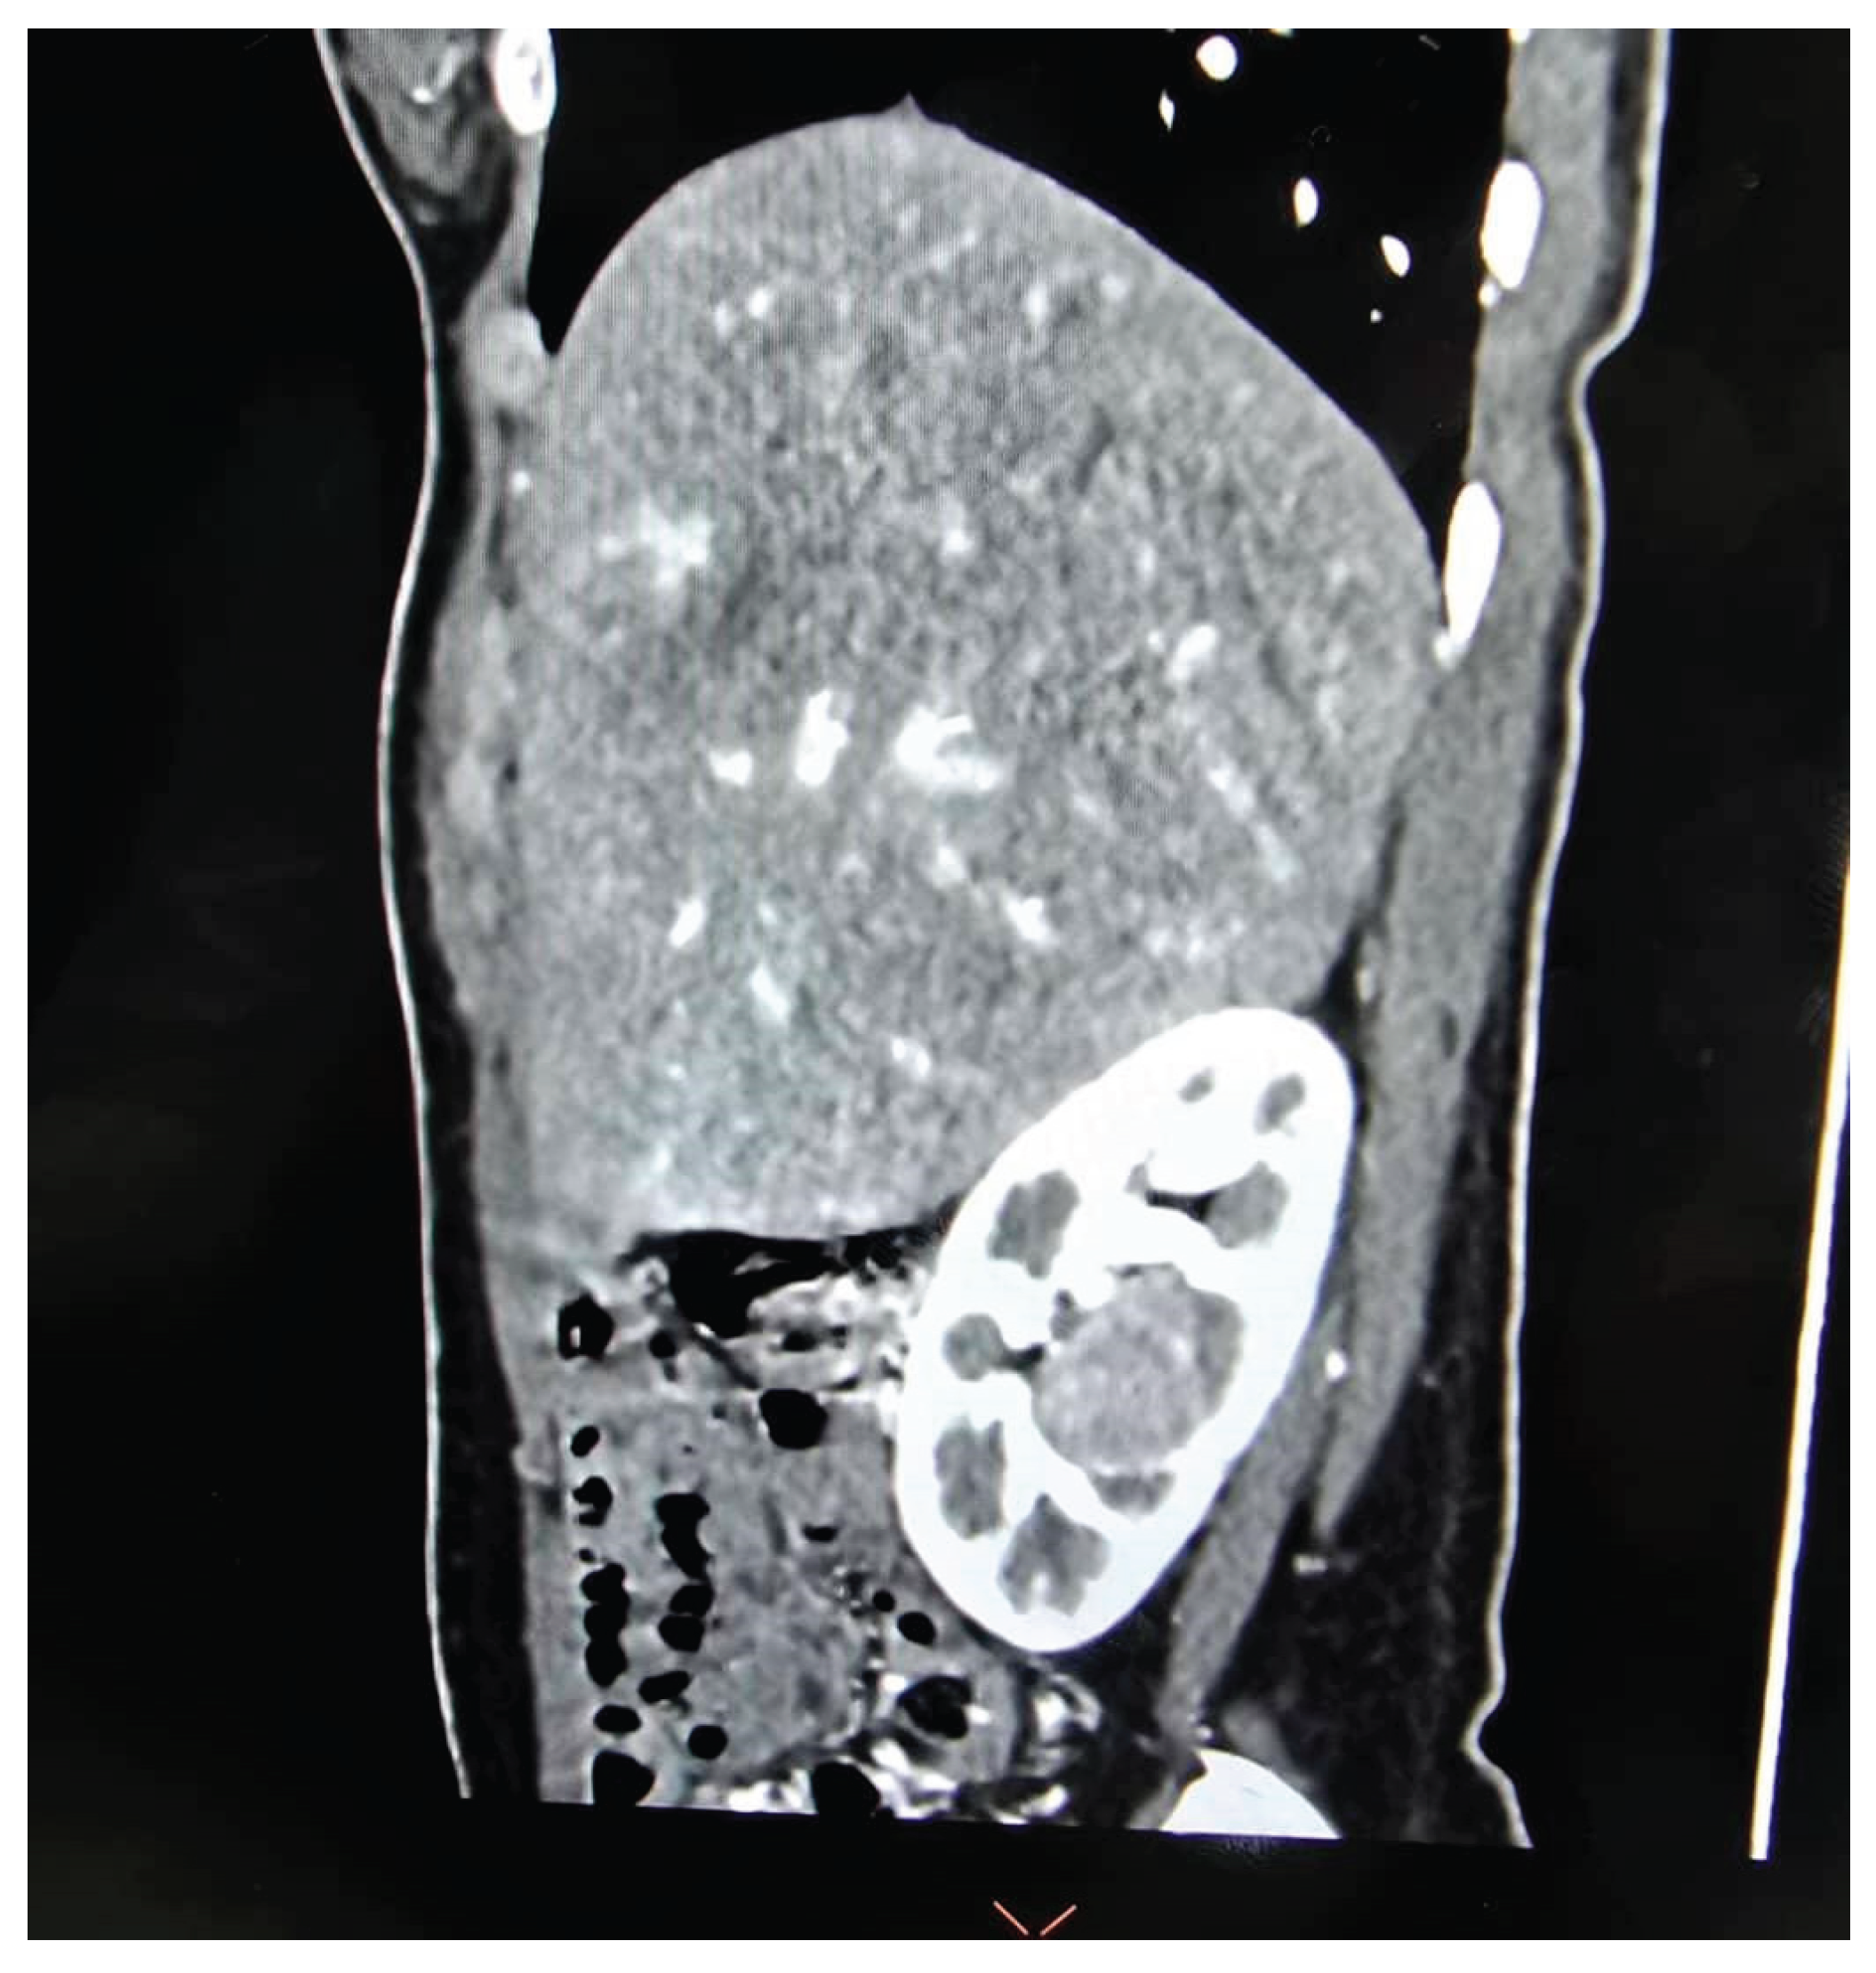

A total of 35 patients, comprising 21 males and 14 females with a mean age of 53.37 ± 15.52 years, underwent RAPN during the study period (Table 1). Tumour characteristics are summarized in Table 2, and perioperative outcomes are detailed in Table 3 and Table 4. All patients had high-complexity tumours, with a median RENAL nephrometry score of 10 (Figure 3A, Figure 3B and Figure 3C).

Figure 3C. Nephrometry score of 10x was given based on the following criteria (R)adius (1 point); (E)ndophytic entirely (3 points); (N)earness < 4mm (3 points); (X)central; and (L)ocation relative to axial line (3 points)